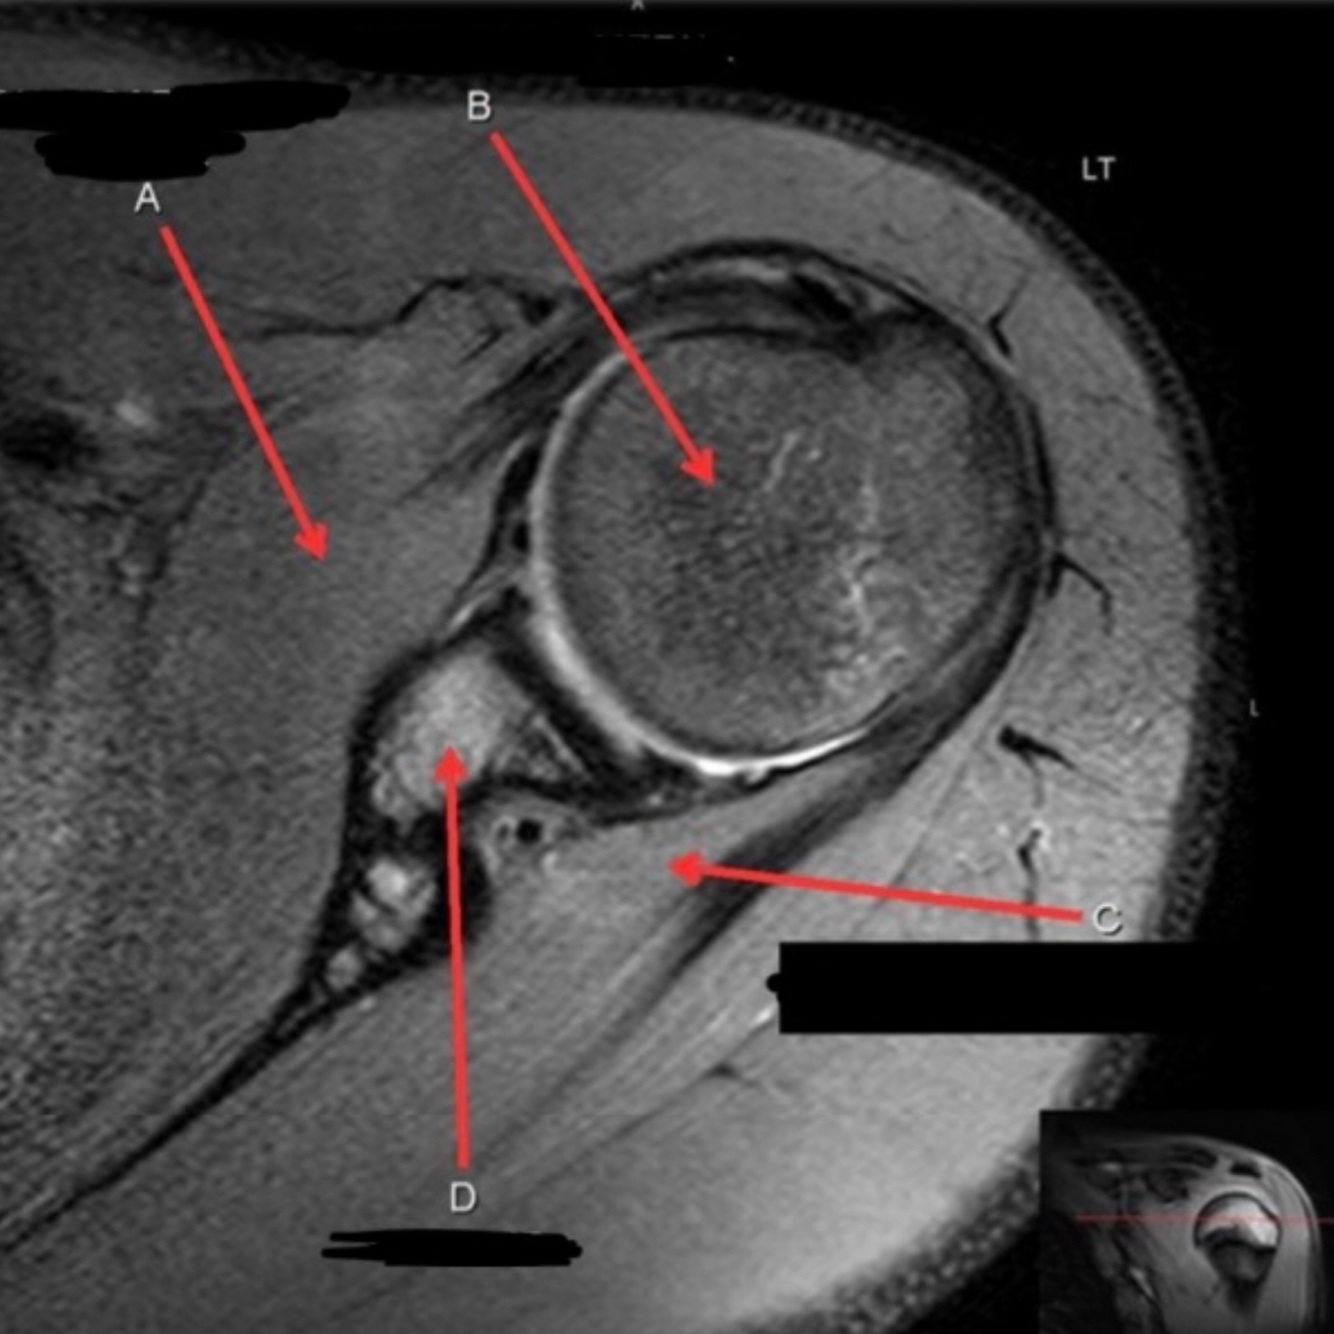

11

Q

What is letter A?

A

ANTERIOR LABRUM

How well did you know this?

1

Not at all

2

3

4

5

Perfectly

12

What is letter B?

BICEPS TENDON (LONG HEAD)

13

What is letter C?

HEAD OF HUMERUS

14

What is letter D?

POSTERIOR LABRUM